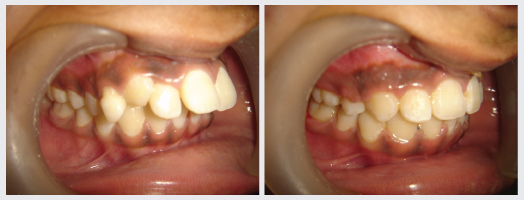

Orthodontics, popularly known as Braces treatment is a speciality of Dentistry that deals with the correction of Malocclusion or Malalignment. It is used to correct crowded teeth, protruded teeth, dental spaces, Jaw Deformities, improper bites and crooked smiles. At DENTAL QUE Orthodontic treatment is done for all age groups and there are types of braces available to suit everyones needs.